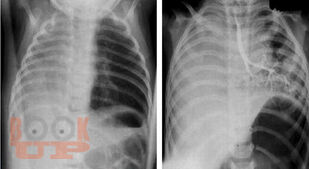

Врожденные аномалии развития легких у детей. Ч. 1

В предлагаемом учебном пособии представлены вопросы эмбриогенеза, классификации, диагностики и способов современного хирургическоголечения некоторых врожденных аномалий лёгких у детей. Учебное пособие соответствует образовательной программе ФГОС ВО 3+ для студентов медицинских вузов, обучающихся по специальностям «Лечебное дело»,«Педиатрия». Учебное пособие предназначено для освоения компетенций ОК-4, ОК-5, ОПК-10, ПК-5, дисциплины «Общая хирургия, хирургические болезни» стоматологического факультета, компетенций ПК-5, ПК-6, ПК-22 дисциплины «Детская хирургия» педиатрического факультета, компетенций ПК-14, ПК-17, ПК-26 дисциплины «Госпитальная хирургия, детская хирургия» лечебного факультета.